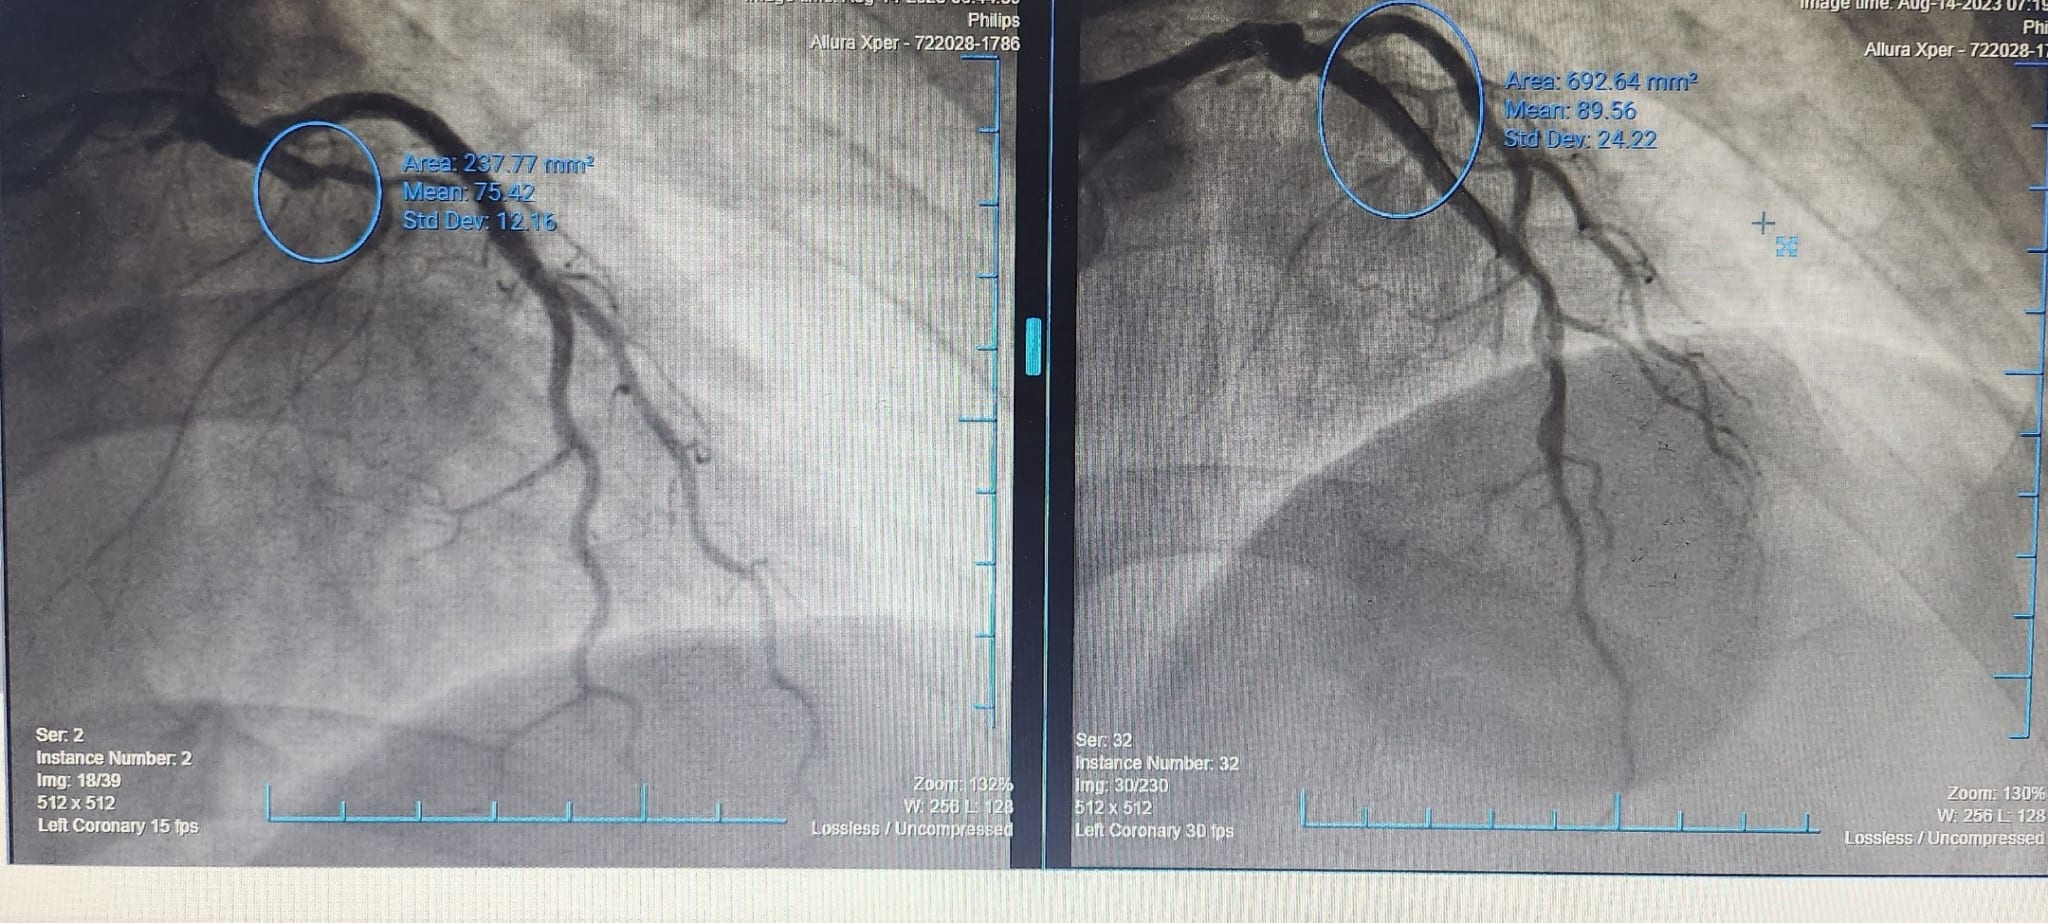

Đúng như dự đoán, kết quả chụp DSA mạch vành của bệnh nhân cho thấy tắc hoàn toàn liên thất trước LAD I do huyết khối trên nền xơ vữa. Ngay lập tức, kíp can thiệp tiến hành can thiệp, đặt stent tái thông dòng máu nuôi tim thành công. Ghi nhận động mạch vành được tái thông hoàn toàn, dòng chảy tốt. Sau can thiệp, bệnh nhân hồi phục nhanh, cải thiện hoàn toàn triệu chứng đau ngực, khó thở.